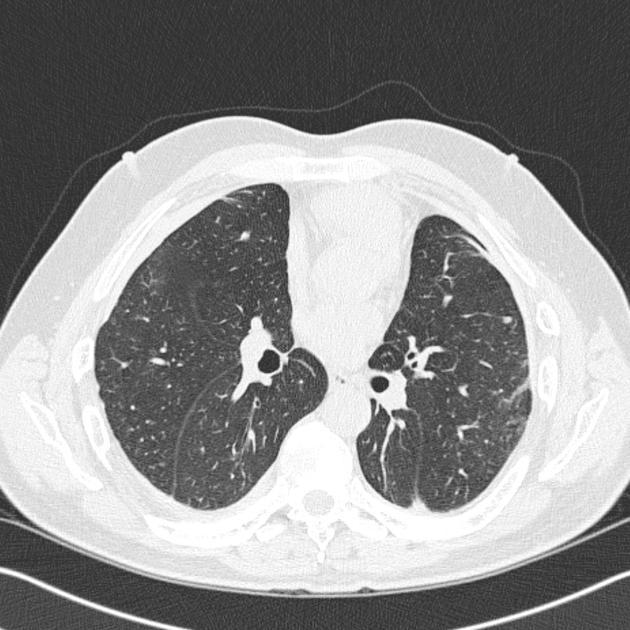

CT

Appearances of asbestosis vary with the duration and severity of the condition. Early manifestations are largely confined to the peripheral region of the lower zones and are subtle. They include:

centrilobular dot-like opacities: peribronchial fibrosis

intralobular linear opacities: reticulation

subpleural lines (often curvilinear)

These changes may be similar in appearance to dependent atelectasis, especially when located posteriorly, and thus supine and prone scans are recommended 3.

As the fibrosis progresses, a number of more definite findings are seen, which continue to be particularly subpleural and lower lung zone in distribution. They include:

parenchymal bands

traction bronchiectasis

honeycomb fibrosis